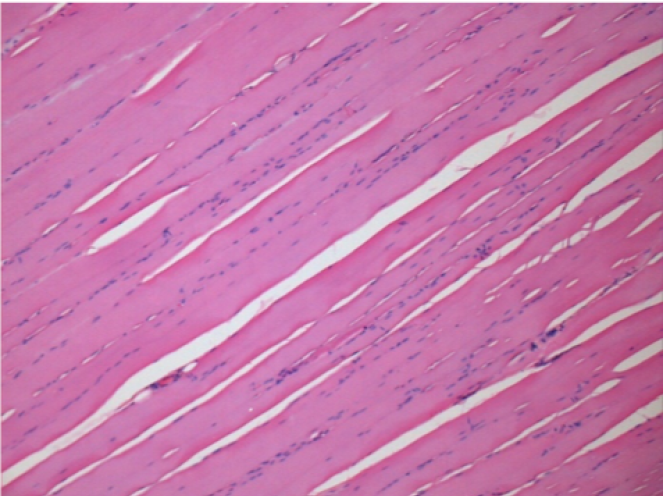

بعد 3 أشهر من حقن إندوبيل

3 أشهر (D90) بعد حقن Endopeel 0.1 مل في العضلة أمام الظنبوب اليمنى.

L : Control-100xD90

R:100xD90